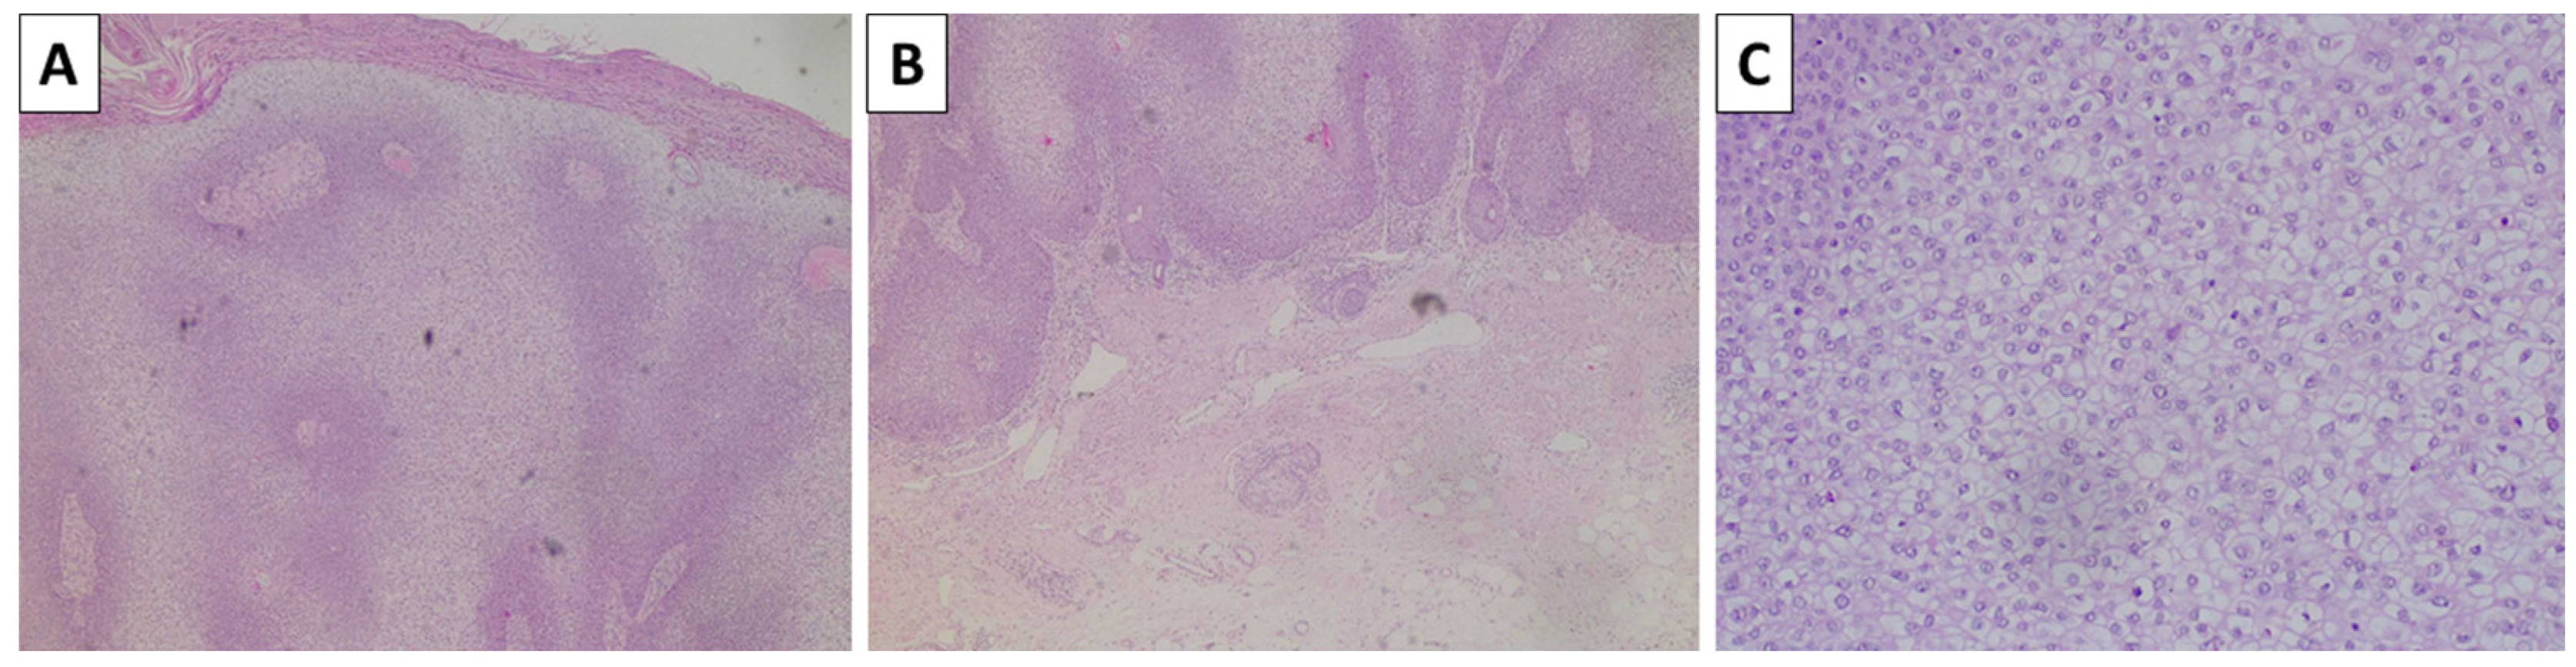

The lesion on the cheek, histologically, was represented by an atrophic epidermis and a melanocyte lesion with well-defined borders involving the epidermis and extending to the reticular dermis, composed of areas of marked pigmentation and cellularity, with oval to spindle-shaped cells with small monomorphic nuclei, speckled chromatin, and more abundant light or finely pigmented cytoplasm. The tumor cells are arranged in short fascicles and nests, surrounded by pigmented macrophages and circumscriptive sclerotic stroma. Hence, the lesion was diagnosed as a cellular blue nevus (Figure 4). The second lesion histologically was represented by an acanthotic lesion comprising large squamoid cells with light cytoplasm and easily identifiable mitoses, forming intraepidermal nests with microabscesses, single concentric keratin deposits, and focal ulceration. Hence, the lesion was diagnosed as a squamous cell carcinoma in situ (Figure 5). No basement membrane penetration was noted with a dense lichenoid infiltrate located under the lesion. The third lesion was histologically represented by a pigmented lesion with an asymmetric profile, comprising a dermally located neoplastic proliferation of epithelioid-type cells that progressed beyond the border of the dermal component, with nesting structures at the dermoepidermal junction and pagetoid spread. The tumor cells exhibited marked pleomorphism and eosinophilic cytoplasm, as well as vesicular nuclei and prominent nucleoli. An abundance of pigmented macrophages accompanied the sparse intervening stroma, and the pigmentation varied from apigmented to coarsely pigmented. No marked lymphocytic infiltrate, necrosis, or erosion of the surface epithelium was noted. However, the lesion extended to the reticular dermis (Clark IV) and had an overall thickness of 3 mm (Breslow stage III), without epidermal ulceration, the presence of vascular emboli, or atypical mitoses less than 5 per square millimeter (Figure 6). The neighboring pigmented lesion was represented by an epidermally based nevomelanocytic lesion comprising poorly pigmented cells and nests in the dermis, featuring nonpigmented nevomelanocytes with focal low-grade cytological atypia. Hence, the lesion was diagnosed as pT3a melanoma. The patient was referred to the oncology committee for treatment and is currently undergoing treatment and monitoring with stable disease and no progression of either the melanocytic or squamous cell neoplasia.

Figure 5.

Histopathology of the auricular lesion. (A,B) acanthotic epidermis with superficial ulceration and no penetration of the basal lamina, original magnification 4×; (C) acanthotic proliferation by atypical keratinocyte with clear cell cytoplasmic change, original magnification 100×; staining (A–C) hematoxylin and eosin.